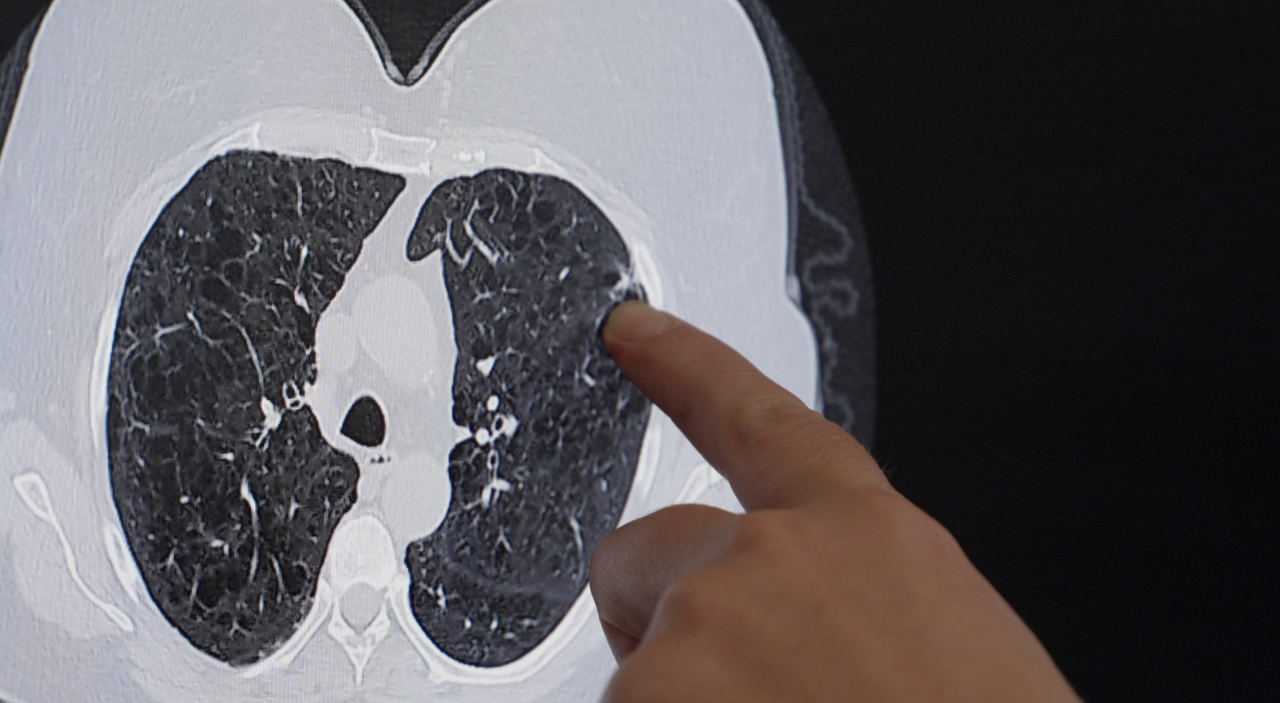

A spot in the upper right corner of Gwyn Lessen’s right lung was cause for concern.

It was only her third lung cancer screening ever. The first in September 2022 was fine. Her second in October 2023 was good. November 2024’s screening revealed a small nodule.

Lessen, a former smoker, was filled with fear but also gratefulness that the tiny lump was caught early. She had surgery at St. Francis this summer.

Dr. Hope Cordova removed the cancer and one third of her lung. Lessen didn’t need chemotherapy or radiation. She just gets follow up scans to monitor her health.

“Gwyn is the perfect example of how best this screening can be utilized,” said Dr. Cordova. “The hope is that when lung cancer is present that we can catch it in an early stage with a small nodule that can be resected before it develops and becomes a more aggressive disease.”